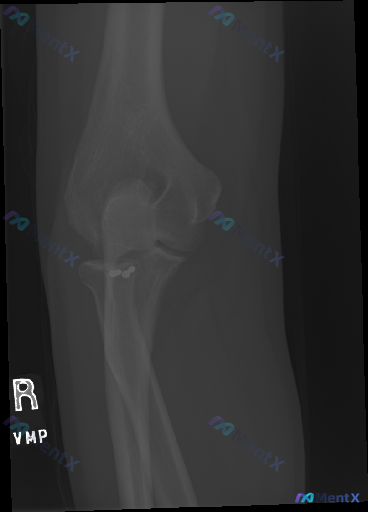

这张右肘关节斜位X光,第一眼容易漏看的高密度影是什么?

整理到一张右肘关节斜位X光的影像资料,先把关键信息放出来:

- 骨性结构:肱骨远端、尺桡骨近端骨皮质连续,关节对合良好,无明确骨折/脱位,脂肪垫征阴性

- 异常发现:在桡骨颈近端内侧、靠近尺骨冠突的区域,有两个边缘锐利、密度明显高于骨骼的类圆形高密度影,有金属伪影特征

- 周围软组织无明显肿胀